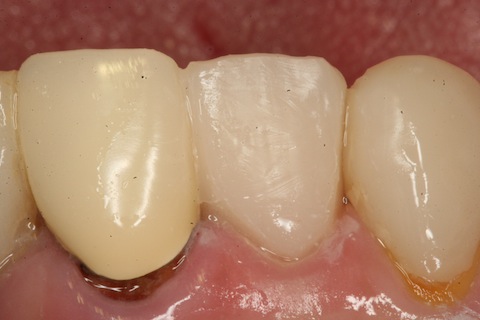

CRで歯冠を作り、

トリミングして終わり。

こんなのでも何年も保つから不思議。。